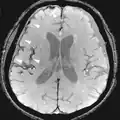

Złogi hemosyderyny wzdłuż wypukłości mózgu, powstałe w wyniku pourazowego krwotoku podpajęczynówkowego.